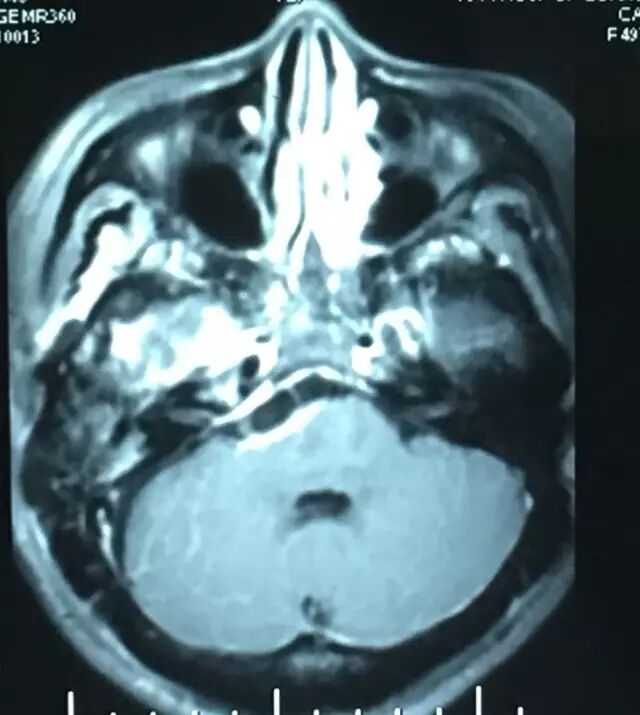

查体:神清语利,双瞳等,光反应灵敏,右侧面部浅感觉减退,行走不稳,四肢肌力基本正常。核磁共振检查见右侧岩斜区肿瘤,考虑岩斜脑膜瘤。

肿瘤强化明显,部分侵入海绵窦。